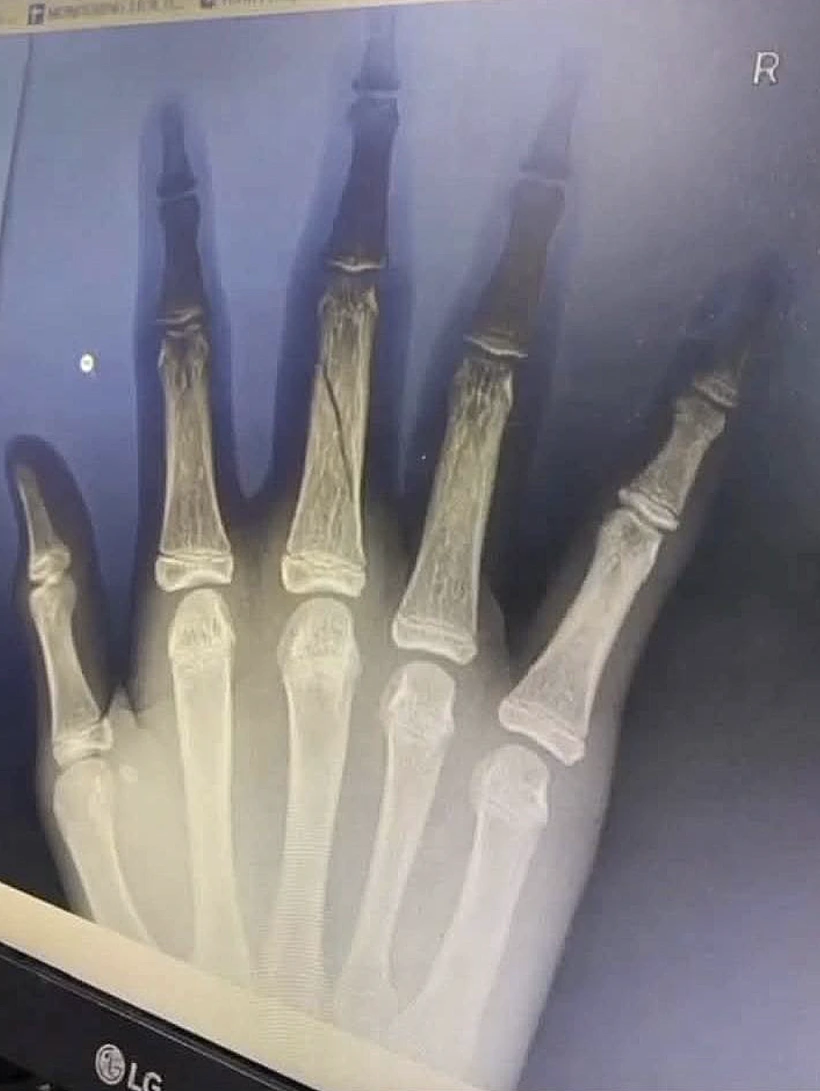

נער בן 13 מאינדונזיה נפל מהמתקן שעמד במהופך באוויר - ונפצע קשה. הוא פונה לבית החולים עם שלושה שברים

על פי הדיווחים, הנער נפל מגובה של כ-2 מטרים ונחבל קשות. הוא פונה לבית חולים עם שני שברים בידו הימנית ושבר נוסף ברגלו.